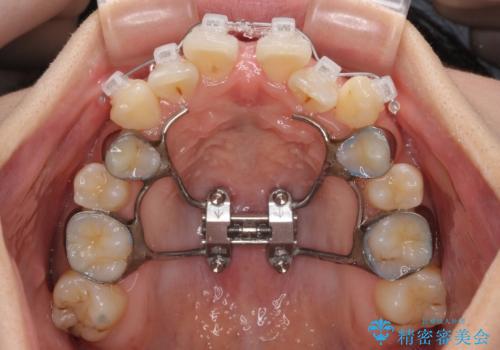

上顎歯列が下顎の歯列に対して狭小であり、一部下顎の奥歯が上顎よりも外側に位置している状態でした。

上顎の急速拡大装置を使用して上顎骨を側方に拡大することで上顎歯列を拡大し、下顎歯列も拡大できるようにすることで、歯列を整えることとしました。

上顎の拡大は、左右どちらに拡大していくのか予想が困難ですが、こちらの患者様では結果として上下正中が一致する方向に拡大され、非常にきれいな仕上がりとなりました。